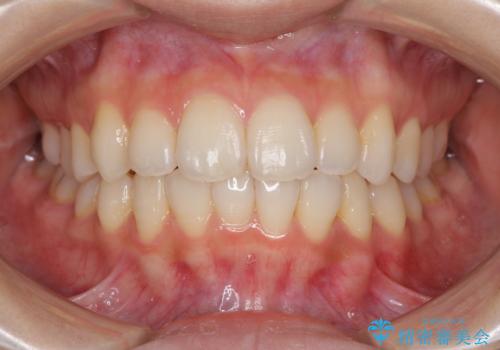

- 前歯のデコボコを気にして来院された患者様です。

叢生と捻転が随所に認められるものの、マウスピースで十分対応可能であったため、インビザラインにて矯正治療を行うこととしました。

マウスピース矯正は毎日しっかりと装着することがとても大切です。

こちらの方はしっかりと指示を守って装着してくださったため、予定通り治療を終えることができました。